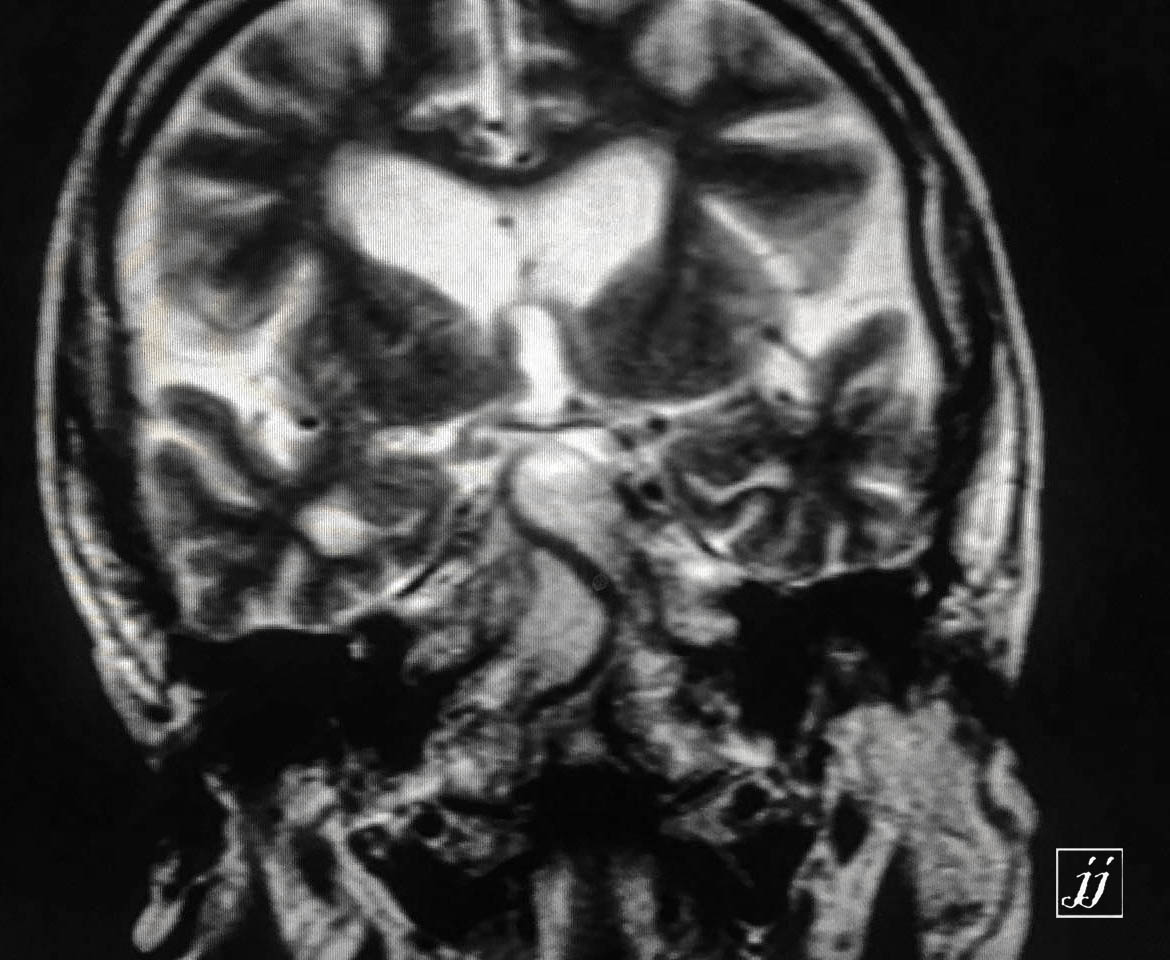

Brain- severe brain atrophy, left neck mass as a carotid body tumor (1)